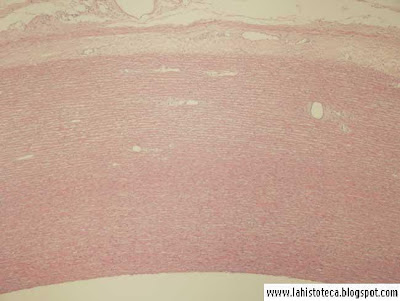

Pared de la aorta (10x )

Encontramos la túnica íntima, media y adventicia.

Observar la microvasculatura propia que desde la adventicia llega hasta cierta profundidad de la túnica media.

También se distingue claramente el endotelio.

Técnica: H&E